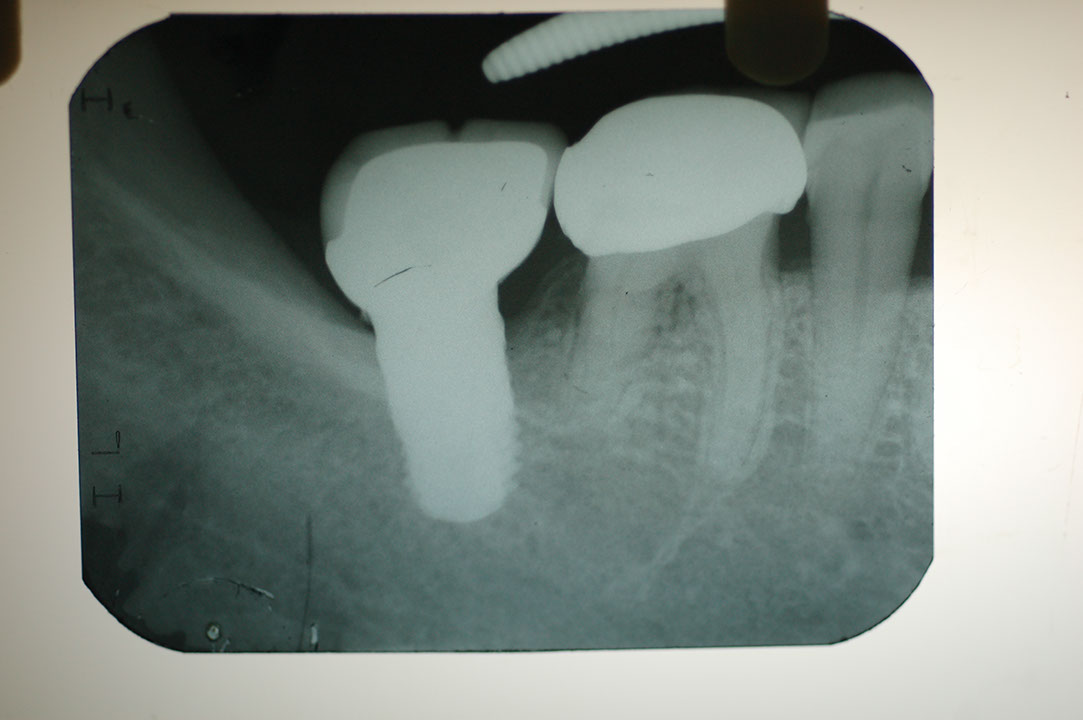

Implant 2f2.JPG

光牙醫